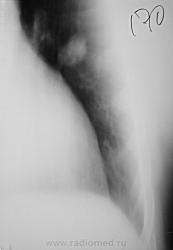

По рентгенографии органов грудной клетки в легких не менее 4 образований... Поскольку живем не в юго-восточной Азии с паразитами, предполагаем в первую очередь метастазы.

Из истории заболевания - оперирована по "женски" чуть больше 1 года назад, получала лучевую терапию....(гинекологи в направлении пишут рак влагалища..